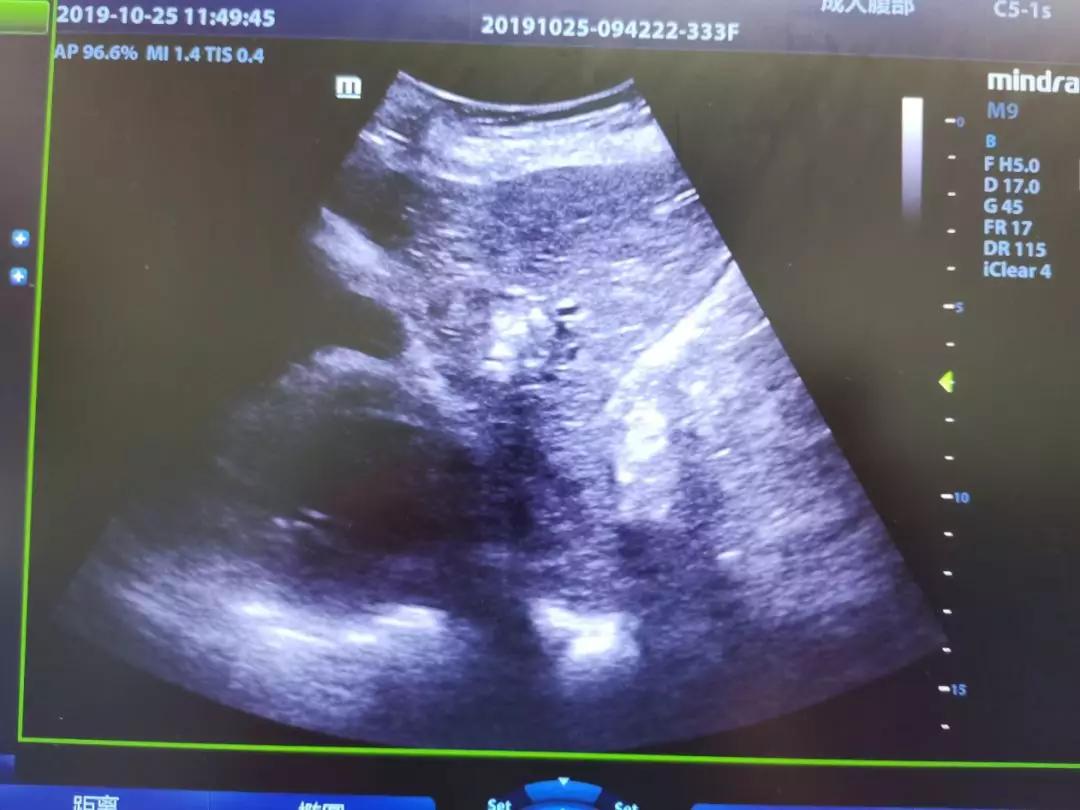

邻近心包的肝癌病灶